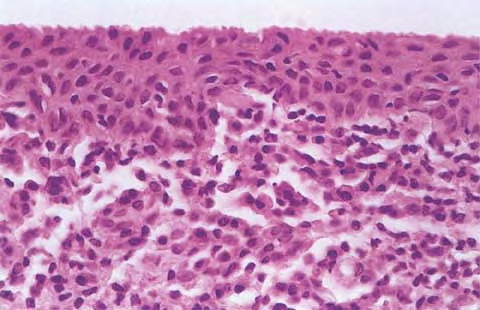

Scondary syphilis = الافرنجي الثانوي